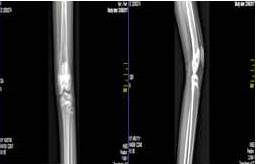

Al cabo de un mes posterior a la realización satisfactoria de quimioterapia (ciclofosfamida, vincristina) la paciente refiere dolor de fuerte intensidad en miembro inferior izquierdo, y aumento de volumen condicionándole limitación para la deambulación (Figura 4) al examen físico se evidencia adenopatías en zona III y IV izquierda, aumento de tumoración en 9o arco costal e induración en región lumbar derecha, en vista de hallazgos se indica radiografía de fémur izquierdo donde se observa reacción perióstica lamelar en capas de cebolla así como imágenes de tipo líticas

La resonancia magnética de muslo izquierdo reporta imágenes heterogéneas nodulares captantes de contraste en la medular de los 2/3 proximales diáfisis y epífisis proximal de fémur izquierdo, con reacción perióstica en el 1/3 medio de dicho hueso. Heterogeneidad en región acetabular bilateral (Figura 6).